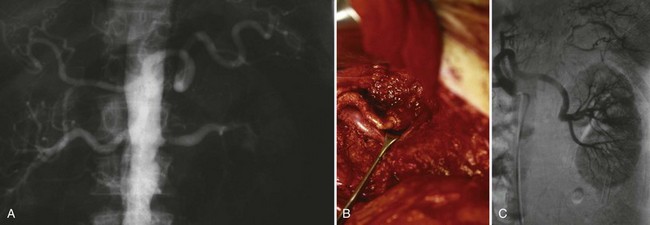

Proposed benefits of preoperative RAE include shrinkage of an arterialized tumor thrombus to ease surgical removal, reduced blood loss, facilitation of dissection due to tissue plane edema, ability to ligate the renal vein before the renal artery at time of nephrectomy, and modulation of the immune response (Klimberg et al, 1985; Bakal et al, 1993; Kalman and Varenhorst, 1999; Schwartz et al, 2007; Wotkowicz and Libertino, 2007; Wszolek et al, 2008). Ligation of the renal vein before the renal artery is useful in the setting of hilar tumors, tumors with significant medial extension, or considerable perihilar adenopathy (Schwartz et al, 2007; Wotkowicz and Libertino, 2007; Wszolek et al, 2008). Before ligating the renal vein, one should characterize the completeness of embolization to prevent unnecessary blood loss in cases of incomplete embolization. In the senior author’s experience this assessment can be made by evaluating renal venous return during surgery. In addition, angioembolization can also be useful for renal tumors associated with large arteriovenous malformations that are having a deleterious hemodynamic impact (Figs. 54-16 and 54-17).

Figure 54–17 A, Left selective renal angiogram demonstrates immediate filling of the renal vein and inferior vena cava. B, Angiogram after placement of coils demonstrates complete angioinfarction. Contrast medium in the contralateral renal pelvis confirms contralateral renal function.